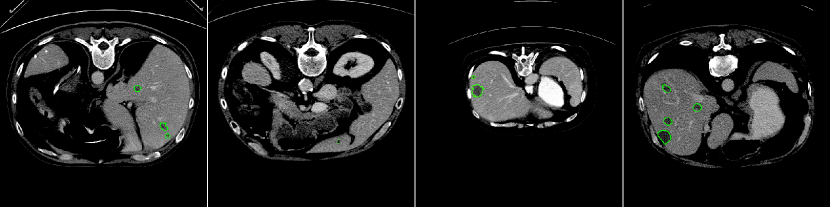

By evaluating on the test set of the LiTS challenge, we list in Table 1 our result with comparison to those of the currently published approaches. According to the Dice score per case, the most important metric for measuring an algorithm’s performance on the LiTS challenge, our approach is at the second rank, following after the H-Dense U-Net [12], which however needs pre-training. In addition, our small lesion segmentation could be an add-on component to their method for a further improvement in segmenting small tumors as mentioned in their future work. Our experiment shows that the dice per case can be improved from 0.61 to 0.681 with the consideration of the small lesion segmentation. Worth to mention that, among the methods without pre-training and post-processing, our method has the best performance in terms of the dice per case score. Figure 7 reports some visual results of our predictions on the LiTS test set.

Observations on LiTS Annotations. As shown in Fig. 6, the LiTS annotations have both over-segmentation and under-segmentation issues. For the large lesions in both cases shown in Fig. 6, our predictions better fit lesions compared to the ground truth; while for the small lesions, our predictions locate more lesions potentially missing in the ground truth. Similar observations have been reported in [4]. Due to the imperfect ground truth provided by the LiTS challenge, we argue that the metrics computed against the ground truth probably could not be the only way to compare the segmentation results. Visual results could be considered as well and ours indicate the efficiency of our method.